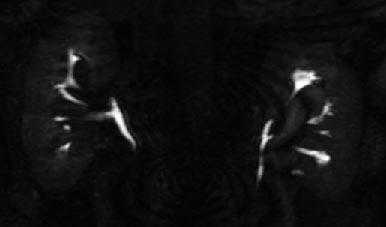

Верблюжий горб

Гиперплазированные колонны Бертини могут выступать из паренхимы, и на УЗИ, на КТ нативных изображениях и нефрографическую фазу возникают подозрения на опухоль почки.

В кортикомедуллярную фазу данные подозрения могут быть опровергнуты. Ниже представлен случай верблюжего горба на УЗИ и КТ.

Представлен другой случай на КТ изображениях в нефрографической фазе есть основания утверждать, что это опухоль, но на кортикомедуллярной становится ясно, что это псевдоопухоль.